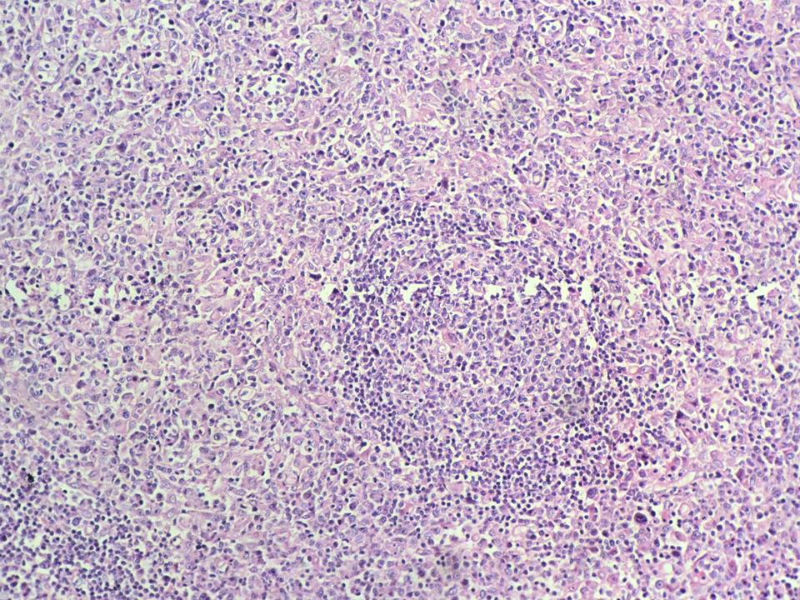

该患者可能存在病毒的感染,抑或是EB病毒的感染,包括CD30+的细胞在内,夹杂在组织细胞、小淋巴细胞之间的一些个大细胞是活化的淋巴细胞,表型看来属B细胞。整个形态呈反应性增生的形态。

Ki-67标记在淋巴滤泡(生发中心)细胞全阳性,而且显示出生发中心边缘规则,不像是肿瘤,呈反应性增生。

Ki-67标记在滤泡间和淋巴组织弥漫增生区见散在阳性细胞,这些阳性细胞可能是转化性淋巴细胞,有的甚至是内皮细胞或组织细胞。

请看下图,显示的细胞比较杂,胞浆较丰富,胞核没有什么特别的异型性。没有促纤维增生反应和围血管生长表现,没有肿瘤性坏死,没有见到更多的核分裂,特别是病理性核分裂。因此认为,本例是淋巴组织反应性增生,可能是对病毒感染的反应。